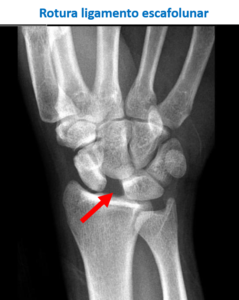

Existen varios ligamentos en la muñeca que pueden lesionarse. El que lo hace de una manera más frecuente es el ligamento escafolunar, que une el escafoides con el semilunar.

Raramente, en algunos esguinces grado III, estará indicado realizar una cirugía para colocar en posición adecuada los huesos y estabilizarlos temporalmente hasta que los ligamentos cicatricen. Esto sucede por ejemplo en algunas luxaciones del hueso semilunar o lesiones del ligamento escafolunar.